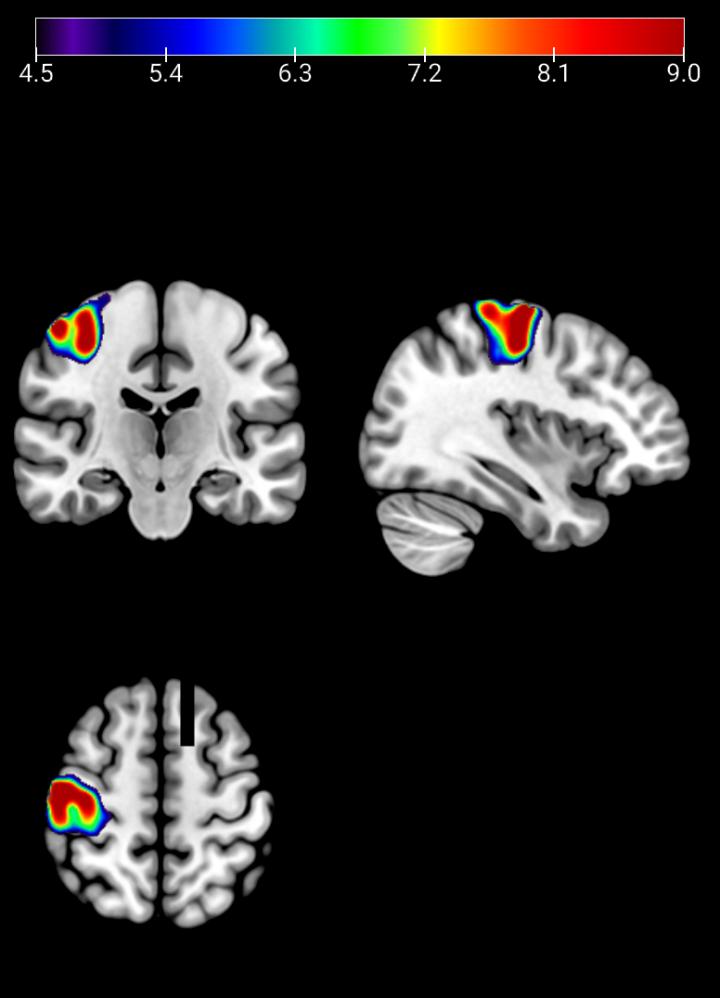

image: Average brain activity during a working memory task in a group of healthy subjects as measured by fMRI. The colors represent higher brain activity in the carriers of the G version of the GCPII enzyme, where brains are less efficient at performing the task, compared with those carriers with the A version of the enzyme.

Finally, they showed that healthy carriers of the G version of the GCPII sequence had less efficient brain activity during a working memory task, as measured by functional MRI, by at least 20% compared with those people with the A version of the gene.